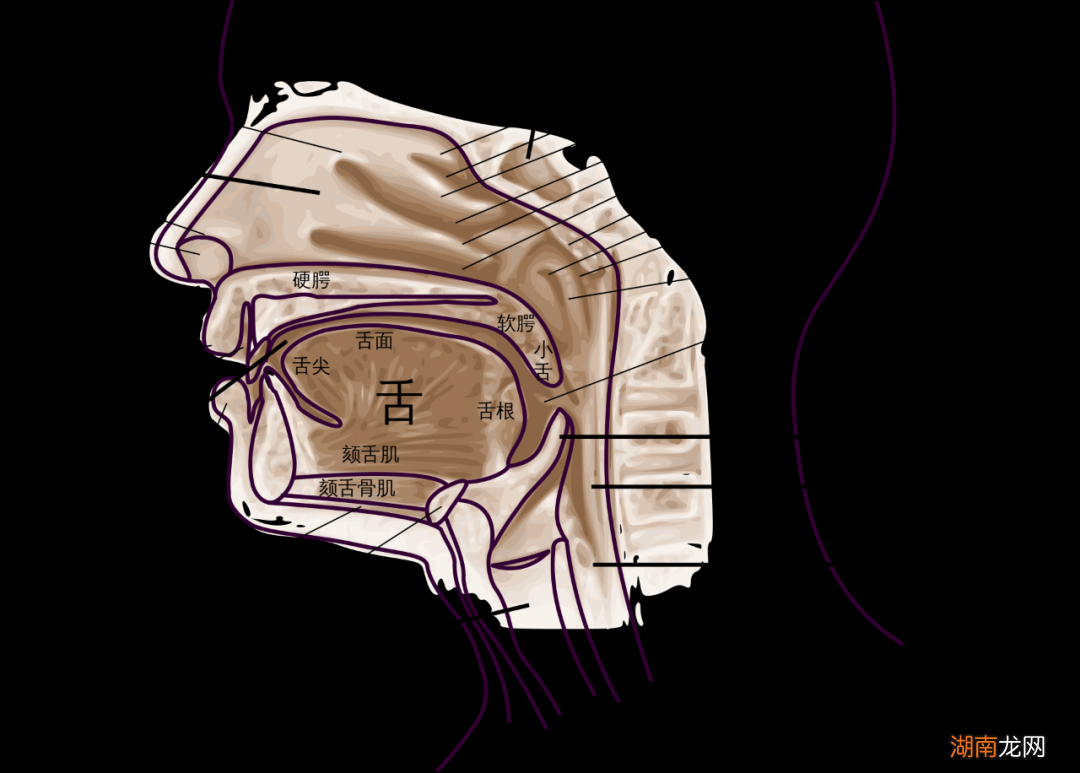

第一个告诉我人类拥有两个鼻子的论点是由罗纳德·埃克尔斯(Ronald Eccles)提出的,他是威尔士卡迪夫大学(Cardiff University)感冒研究中心的鼻腔专家,直到几年前退休 。我知道这听起来很荒谬,但请考虑一下你的鼻子,或者说你的两个鼻子在内部是什么样子:每个鼻孔通向自己的鼻腔,不直接与另一个鼻孔相连接 。它们是两个独立的器官,就像你的两只眼睛或两只耳朵一样 。

鼻子远非被动的通道 , 它隐藏着不断变化的内部结构 。正如埃克尔斯所说,鼻子内部有静脉勃起组织,其结构“与阴茎的勃起组织相似”,并且会充血 。感染或过敏会加剧肿胀,以至于鼻腔会完全堵塞 。

? NHPR

与我们的眼睛、耳朵和嘴巴不同,鼻子必须每天24小时都在工作,不断地为我们脆弱的肺部组织过滤和加热空气 。鼻子的工作听起来可能没那么难 , 但考虑一下它必须做什么:我们呼吸的空气温度可能为70华氏度(约21摄氏度),湿度为35%,“当空气进入我的鼻子并返回我的鼻咽部(大约三到四英寸)时 , 温度已达到98.7华氏度(约37摄氏度),湿度为100% 。”鼻子是一个非常强大的小型暖通空调系统 。

在某种程度上 , 我们都是自己鼻塞不可靠的叙述者 。当患者前去接受检查时,医生可能会看到他们一侧鼻子明显比另一侧更肿胀,但这未必是患者感到更堵塞的那一侧 。“这仍然让临床医生感到困惑 。”史密斯告诉我 。其他因素,比如温度,也可能起到一定作用 。鼻子的内部结构复杂而神秘 。下次我如果再次病倒 , 再次感到堵塞时,我会思考所有这些事情 。